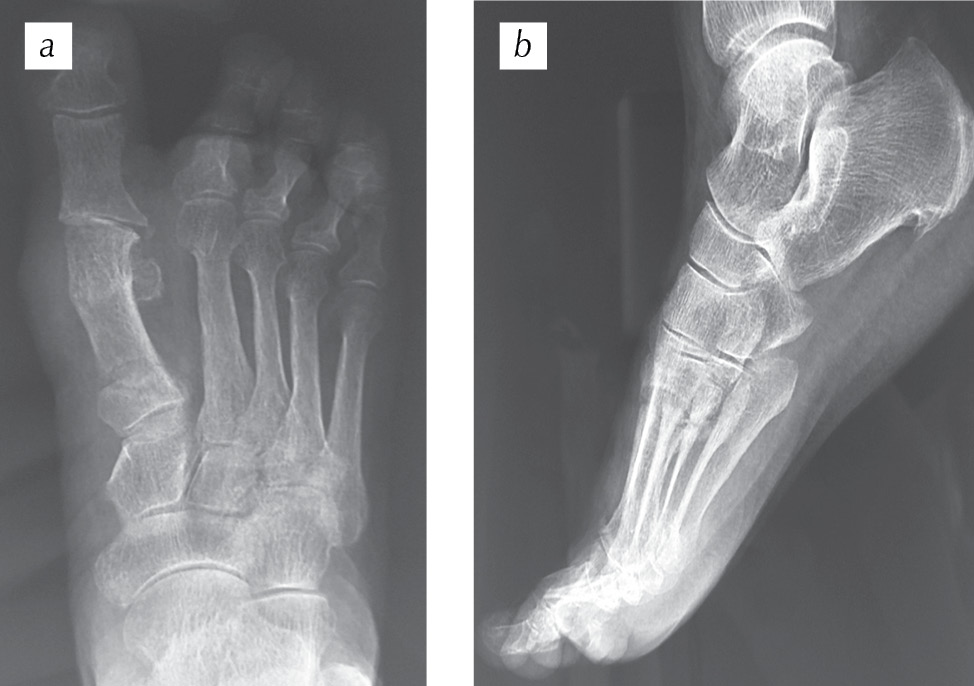

На рис. 4 представлены рентгенограммы пациентки в двух проекциях сразу после оперативного лечения. Угол вальгусного отклонения I пальца, образованный осями I плюсневой кости и проксимальной фаланги I пальца, равен 8° при норме 8–16°. Межфаланговый угол I пальца, образованный осями проксимальной и дистальной фаланг I пальца, равен 0° при норме 0–8°. Угол варусного отклонения I плюсневой кости, образованный осями I и II плюсневых костей, равен 13° при норме 5–14°. Угол наклона суставной поверхности головки I плюсневой кости, образованный осью I плюсневой кости и осью, проведенной перпендикулярно линии, соединяющей края суставной поверхности головки I плюсневой кости, равен 10° при норме 3–10°. Угол наклона суставной поверхности основной фаланги к ее оси, образованный проксимальной фалангой I пальца и перпендикуляром к плоскости суставной поверхности этой же фаланги, равен 0° при норме 0–5°. Угол наклона суставной поверхности медиального плюснеклиновидного сустава, определяемый как угол между линией данного сустава и перпендикуляром к тангете медиального края медиальной клиновидной кости, равен 20° при норме 0–20°.

Рис. 4. Рентгенограммы переднего отдела правой стопы пациентки Е. сразу после оперативного лечения: а — прямая проекция; b — косая (3/4) проекция (пояснения см. в тексте)

Fig. 4. Radiographs of the anterior part of the right foot of patient E. immediately after the surgery: а — straight projection; b — oblique (3/4) projection (see the text for explanations)